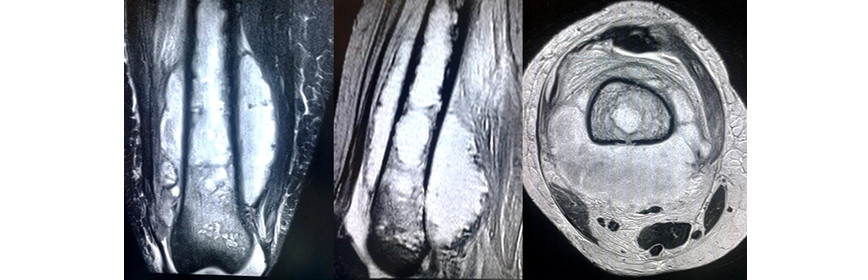

La RMN del muslo derecho con contraste endovenoso (Fig. 5) en secuencias coronal, sagital y transversal, mostró una extensa masa de aspecto heterogéneo, realzada con la administración del medio de contraste (Dotarem) localizada predominantemente en el tercio distal del muslo, que invadía el canal medular, asociada con osteolisis y periostitis.

Fig. 5 - Resonancia magnética nuclear del muslo derecho con contraste endovenoso. Se observa una masa de aspecto heterogéneo, que invade el canal medular, asociada con osteolisis y periostitis.